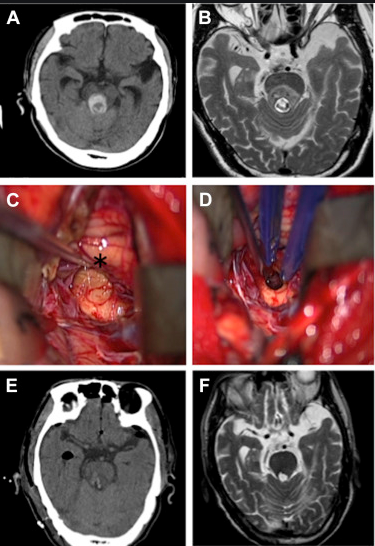

那么如何提高腦干海綿狀血管瘤生存期呢?前面也說了,想要提高生存期,擁有一個長的生命,及時治療是需的。而對于腦干海綿狀血管瘤的治療手術(shù)是主要手段,其中手術(shù)切除率的高低主要決定了治療效果,理想狀態(tài)下是全切,這樣才能確定不復(fù)發(fā)。目前手術(shù)主要包括傳統(tǒng)手術(shù)和顯微外科手術(shù),但傳統(tǒng)手術(shù)切除率往往不能達到很理想的狀態(tài),因為憑借肉眼觀察,很多時候往往并不能清楚的看清腫瘤所在,達不到一個理想的切除率。而顯微外科手術(shù)借助于手術(shù)顯微鏡的放大,再結(jié)合神經(jīng)導(dǎo)航、術(shù)中MRI、術(shù)中超聲等輔助設(shè)備,視野更清晰、入路豐富,細致的顯微手術(shù)器械及縫合材料,讓血管瘤切除率達到更高,手術(shù)順利性更有保障,創(chuàng)傷面積更小,并且患者生存率都有所提高。

海綿狀血管瘤一般位置都不會固定的出現(xiàn)在同一個地方,每個人的腦海綿狀血管瘤位置都會有所差異。以往的手術(shù)治療入路單一,創(chuàng)傷面積大,而國際腫瘤顱底手術(shù)教授巴特朗菲教授擁有20年的腦干海綿狀血管瘤的外科治療經(jīng)驗,可以從多種入路更好的靠近多區(qū)域的腫瘤進行切除,減少患者術(shù)后的痛苦,減低感染的風險。術(shù)后,37%的患者表現(xiàn)出短暫的(輕微)神經(jīng)功能缺損,其余超過90%的患者,神經(jīng)功能與術(shù)前持平或好轉(zhuǎn)。

在巴特朗菲教授一份關(guān)于72名海綿狀血管瘤患者研究報告中顯示,在顯微外科手術(shù)后的72人中,大部分患者沒有再出血等其他不良癥狀,術(shù)后生活質(zhì)量得以明顯好轉(zhuǎn)。

參考文獻:Tsuji Y, Kar S, Bertalanffy H. Microsurgical Management of Midbrain Cavernous Malformations: Predictors of Outcome and Lesion Classification in 72 Patients[J]. Operative Neurosurgery, 2019.